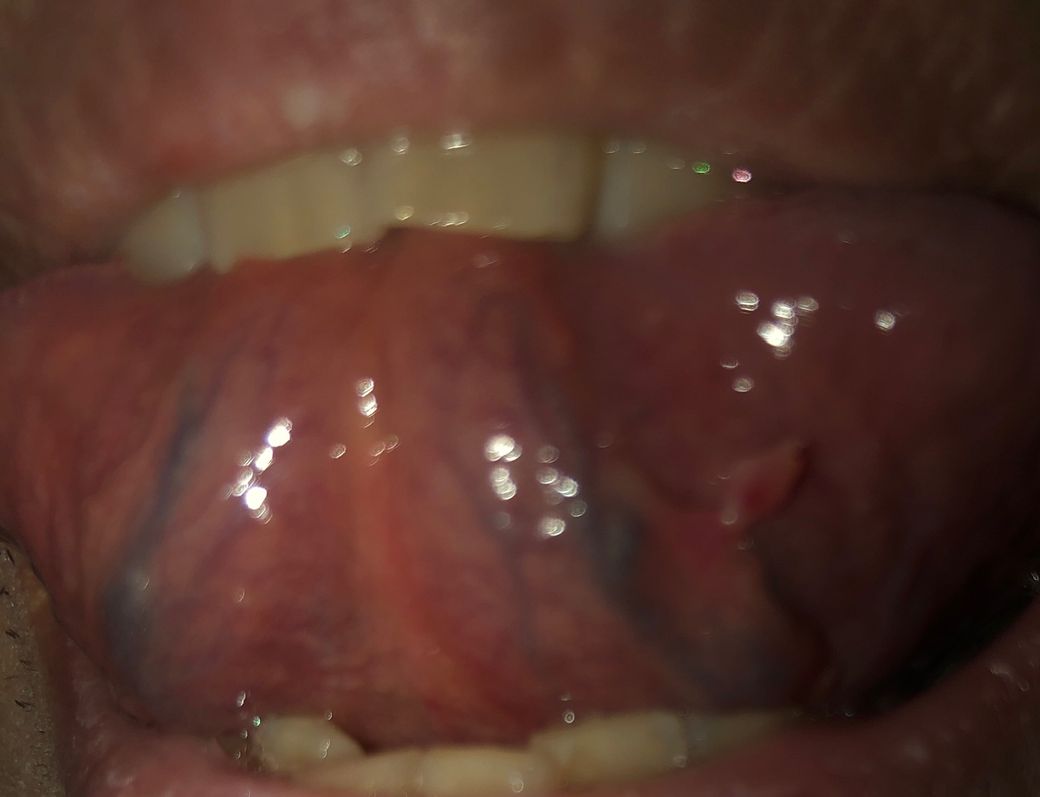

혀바닥이 아프네요 이거 왜이런걸까요..?

저기 오른쪽에 혼자만 동떨어진 혀바닥잇는데 치아에 걸려서 뜯어진건지.. 덜렁덜렁 살점 떨어지는거처럼 그러는데 만지면 막 아프지는 않고 밥먹을때 좀 아파서 불편한데 저거 병원가면 마추ㅏ하고 살점 떼자고 할려나요?? ㅠㅠ 하 안아픈거 약이라도잇을까요?? 치아는 아니니까 이비인후과 가야하는거맞죠?

설명하신 양상으로 보면 가장 가능성이 높은 것은 혀 하부 점막의 외상성 병변입니다. 치아에 반복적으로 걸리거나 씹히면서 점막이 부분적으로 찢어져 부종이 생기면 덜렁거리는 살점처럼 느껴질 수 있습니다. 통증이 심하지 않지만 음식 섭취 시 불편한 것도 전형적인 소견입니다.

이 경우 병태생리는 단순 기계적 자극에 의한 점막 손상이며, 임상적으로는 외상성 궤양 또는 점막 플랩 형태로 보입니다. 대부분 감염이나 종양과는 무관합니다.

진단은 이비인후과에서 육안 진찰로 충분한 경우가 대부분입니다. 크기가 작고 점차 가라앉는 양상이면 추가 검사 없이 경과 관찰을 권합니다. 외래에서 바로 살점을 떼어내는 처치는 보통 하지 않으며, 괴사되었거나 회복을 방해할 정도로 큰 경우에만 국소 처치를 고려합니다.

치료는 보존적 치료가 원칙입니다. 자극을 최소화하고, 자극적인 음식·술·흡연은 피하는 것이 중요합니다. 증상 완화를 위해 국소 진통·소염 성분의 구강용 겔이나 가글제를 사용할 수 있으며, 대부분 1주에서 2주 사이에 호전됩니다.

2주 이상 지속되거나 크기가 커지거나, 단단하게 만져지거나, 출혈이 반복되면 반드시 이비인후과 진료를 보시는 것이 적절합니다. 현재 상황에서는 이비인후과 방문이 맞습니다.